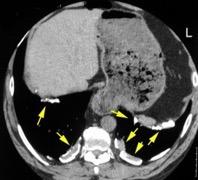

Absceso secundario a perforación de carcinoma. 3-4%. En flexura esplénica puede tener absceso subfrénico o empiema.

Empiema pleural secundario a carcinoma de la flexura esplénica (masa visible)

Lian R et al. Empyema caused by a colopleural fistula. Medicine (Baltimore) 2017/Osada T,, et al. Thoracic empyema associated with recurrent colon cancer: report of a case and review of the literature. Dis Colon Rectum 2001